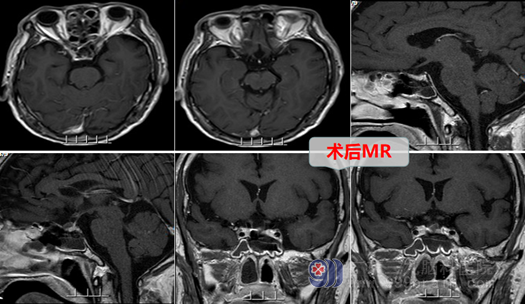

外十科团队经过详细病情讨论,决定采用微创技术全麻下行内镜经鼻蝶鞍区rathke囊肿开窗引流术,术中磨除鞍底骨窗约1.5cm大小,钩刀“+字型”全层切开硬脑膜。见病变囊内容物灰白色,正常垂体组织位于下后方,鞍膈塌陷,流出全部囊液,切除部分囊壁,检查无脑脊液漏,无明显出血,顺利结束手术。术后复查头颅CT示鞍区病变切除满意,未见积血,加行了药物对脑梗塞的治疗。几天后,汤叔汤叔迅速好转,也未出现尿崩、头痛等症状。